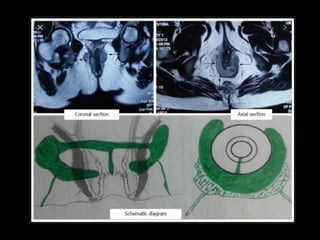

a = anal canal, IAF = ischioanal fossa, IRF = ischiorectal fossa, R = rectum

Line diagram shows the normal anatomy of the perianal region in the

• MR Imaging of Perianal Fistulas Normal Anatomy

The anatomy of the perianal region is well

demonstrated on coronal and axial MR images

(Fig 4).

• The internal and external sphincters are not

separately resolved in normal subjects on MR

images obtained with a body coil,

but the sphincter complex, ischiorectal fossae,

and levator ani sling are clearly seen.